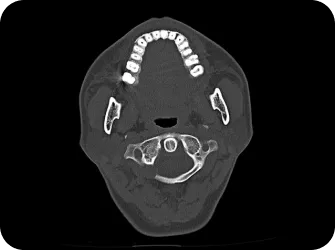

척추 엑스레이 검사

상부경추 1,2번 CT